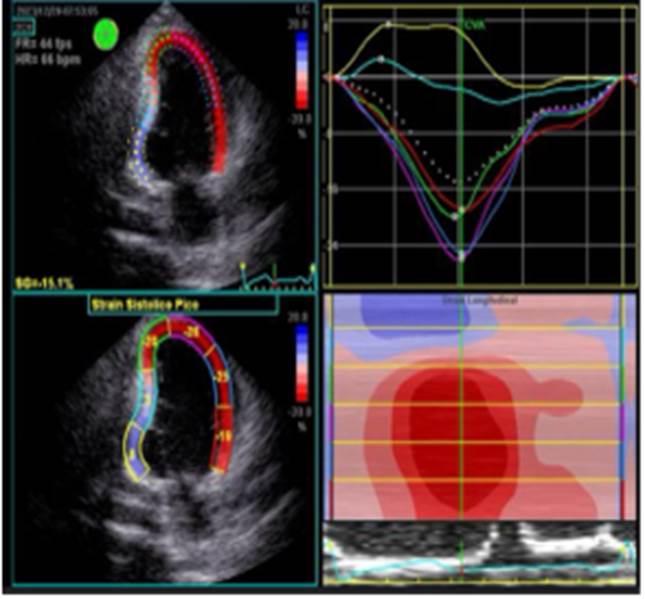

Aproximadamente 3 Semanas posterior al alta presenta cuadro de insuficiencia respiratoria asociado a insuficiencia cardiaca descompensada por lo que acude a nuestro Hospital de Especialidades Abel Gilbert Pontón siendo internada en Unidad Coronaria, a su ingreso se evidencia dolor precordial y torácico bilateral que irradia a región dorsal acompañado de disnea clase funcional NYHA IV/IV, tos persistente y edema leve de miembros inferiores, los laboratorios realizados evidencian anemia leve con hb 10.8 g/dL, péptido natriurético elevado de 12895 pg/ml, enzimas cardiacas negativas, hematuria y proteinuria en uroanálisis; en la radiografía de tórax se muestra cardiomegalia y derrame pleural bilateral; En electrocardiograma taquicardia sinusal, dextrorrotación, complejo QS en cara inferior, sin alteraciones de la onda T y segmento ST. En eco de pleura muestra derrame pleural derecho de moderada a gran cuantía y derrame pleural izquierdo moderado, sospechando de colagenopatía vs enfermedad autoinmune a descartar. Se realiza ecocardiograma transtorácico se evidencia formación aneurismática del VI de 9.5cm x 9.7cm tapizado por trombos con pérdida de la continuidad a nivel perimembranoso septal, además de una miocardiopatía dilatada con FEVI (fracción de eyección del ventrículo izquierdo) 28%. El estudio de líquido pericárdico da como resultado exudado con relación líquido/sérica de LDH 1,8 y proteína 0,7. En ecocardiograma transesofágico (Ilustración 1,2,3) se confirma pseudoaneurisma de gran tamaño del VI en región basal posterior con flujo bidireccional de 10 cm x 7,22cm tapizado de formación trombótica con pérdida de la continuidad de la región basal y posterior del VI con hipocinesia global e hipertensión pulmonar leve con insuficiencia mitral y tricuspidea leve por lo que se decide resolución quirúrgica.

Ilustración 1 Ecocardiograma Transesofágico. Pseudoaneurisma del VI en su porción septal

Fuente: Hospital de Especialidades Guayaquil “Doctor Abel Gilbert Pontón”.

Autor: Dra. María Sánchez Sánchez.

Posterior al alta se realizan controles por consulta externa en nuestro hospital, paciente con mejoría clínica marcada que se evidencia en la tolerancia al decúbito dorsal presentando además cambios beneficiosos en su clase funcional de la NYHA I/IV, en su FEVI al doble en comparación a la FEVI inicial, se mantiene medicación ambulatoria para insuficiencia cardiaca. El control ecocardiográfico 3 meses posteriores al evento muestra trastornos de motilidad en cara inferior con un strain sistólico pico GLPS: -13.5%, mejoría de la FEVI del 44% ilustación 8 y Fig 9, ya no se visualiza Pseudo Aneurisma del septum interventricular persistiendo una pequeña alteración morfológica de la pared inferior del VI que se confirma con la deformidad pico longitudinal disminuida a predominio de la pared inferior basal.

Ilustración 8 Strain sistólico

Ecocardiografía posterior a cirugía donde evidencia área discinética como secuela de reparación quirúrgica Fig 8 y 9.